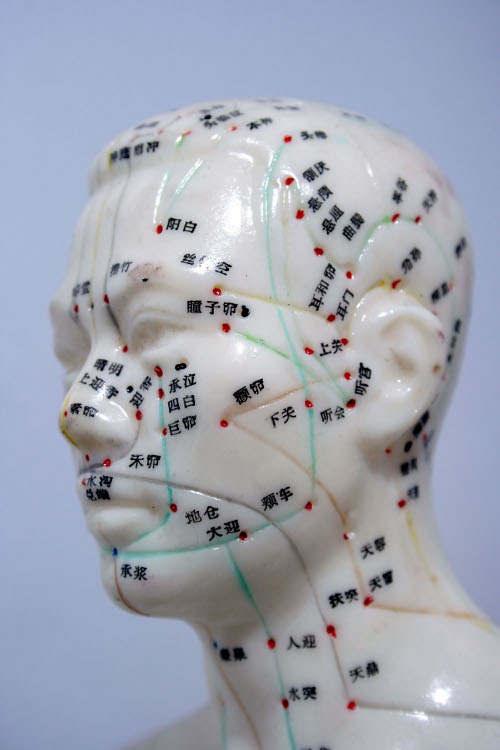

Gli aghi utilizzati nell’agopuntura aiutano ad alleviare i dolori grazie al fatto che innescano nell’organismo la produzione di una sostanza chimica, l’adenosina, di fatto un vero e proprio antidolorifico naturale.

Lo rivelano sulla rivista Nature Neuroscience i ricercatori del Center for Translational Neuromedicine presso il Medical Center dell’Università di Rochester, che inoltre suggeriscono come l’agopuntura potrebbe essere doppiamente efficace se associata ad una terapia a base di deossicoformicina, un farmaco antitumorale che sembra avere la capacità di mantenere alti i livelli di adenosina nell’area trattata.

Lo rivelano sulla rivista Nature Neuroscience i ricercatori del Center for Translational Neuromedicine presso il Medical Center dell’Università di Rochester, che inoltre suggeriscono come l’agopuntura potrebbe essere doppiamente efficace se associata ad una terapia a base di deossicoformicina, un farmaco antitumorale che sembra avere la capacità di mantenere alti i livelli di adenosina nell’area trattata.